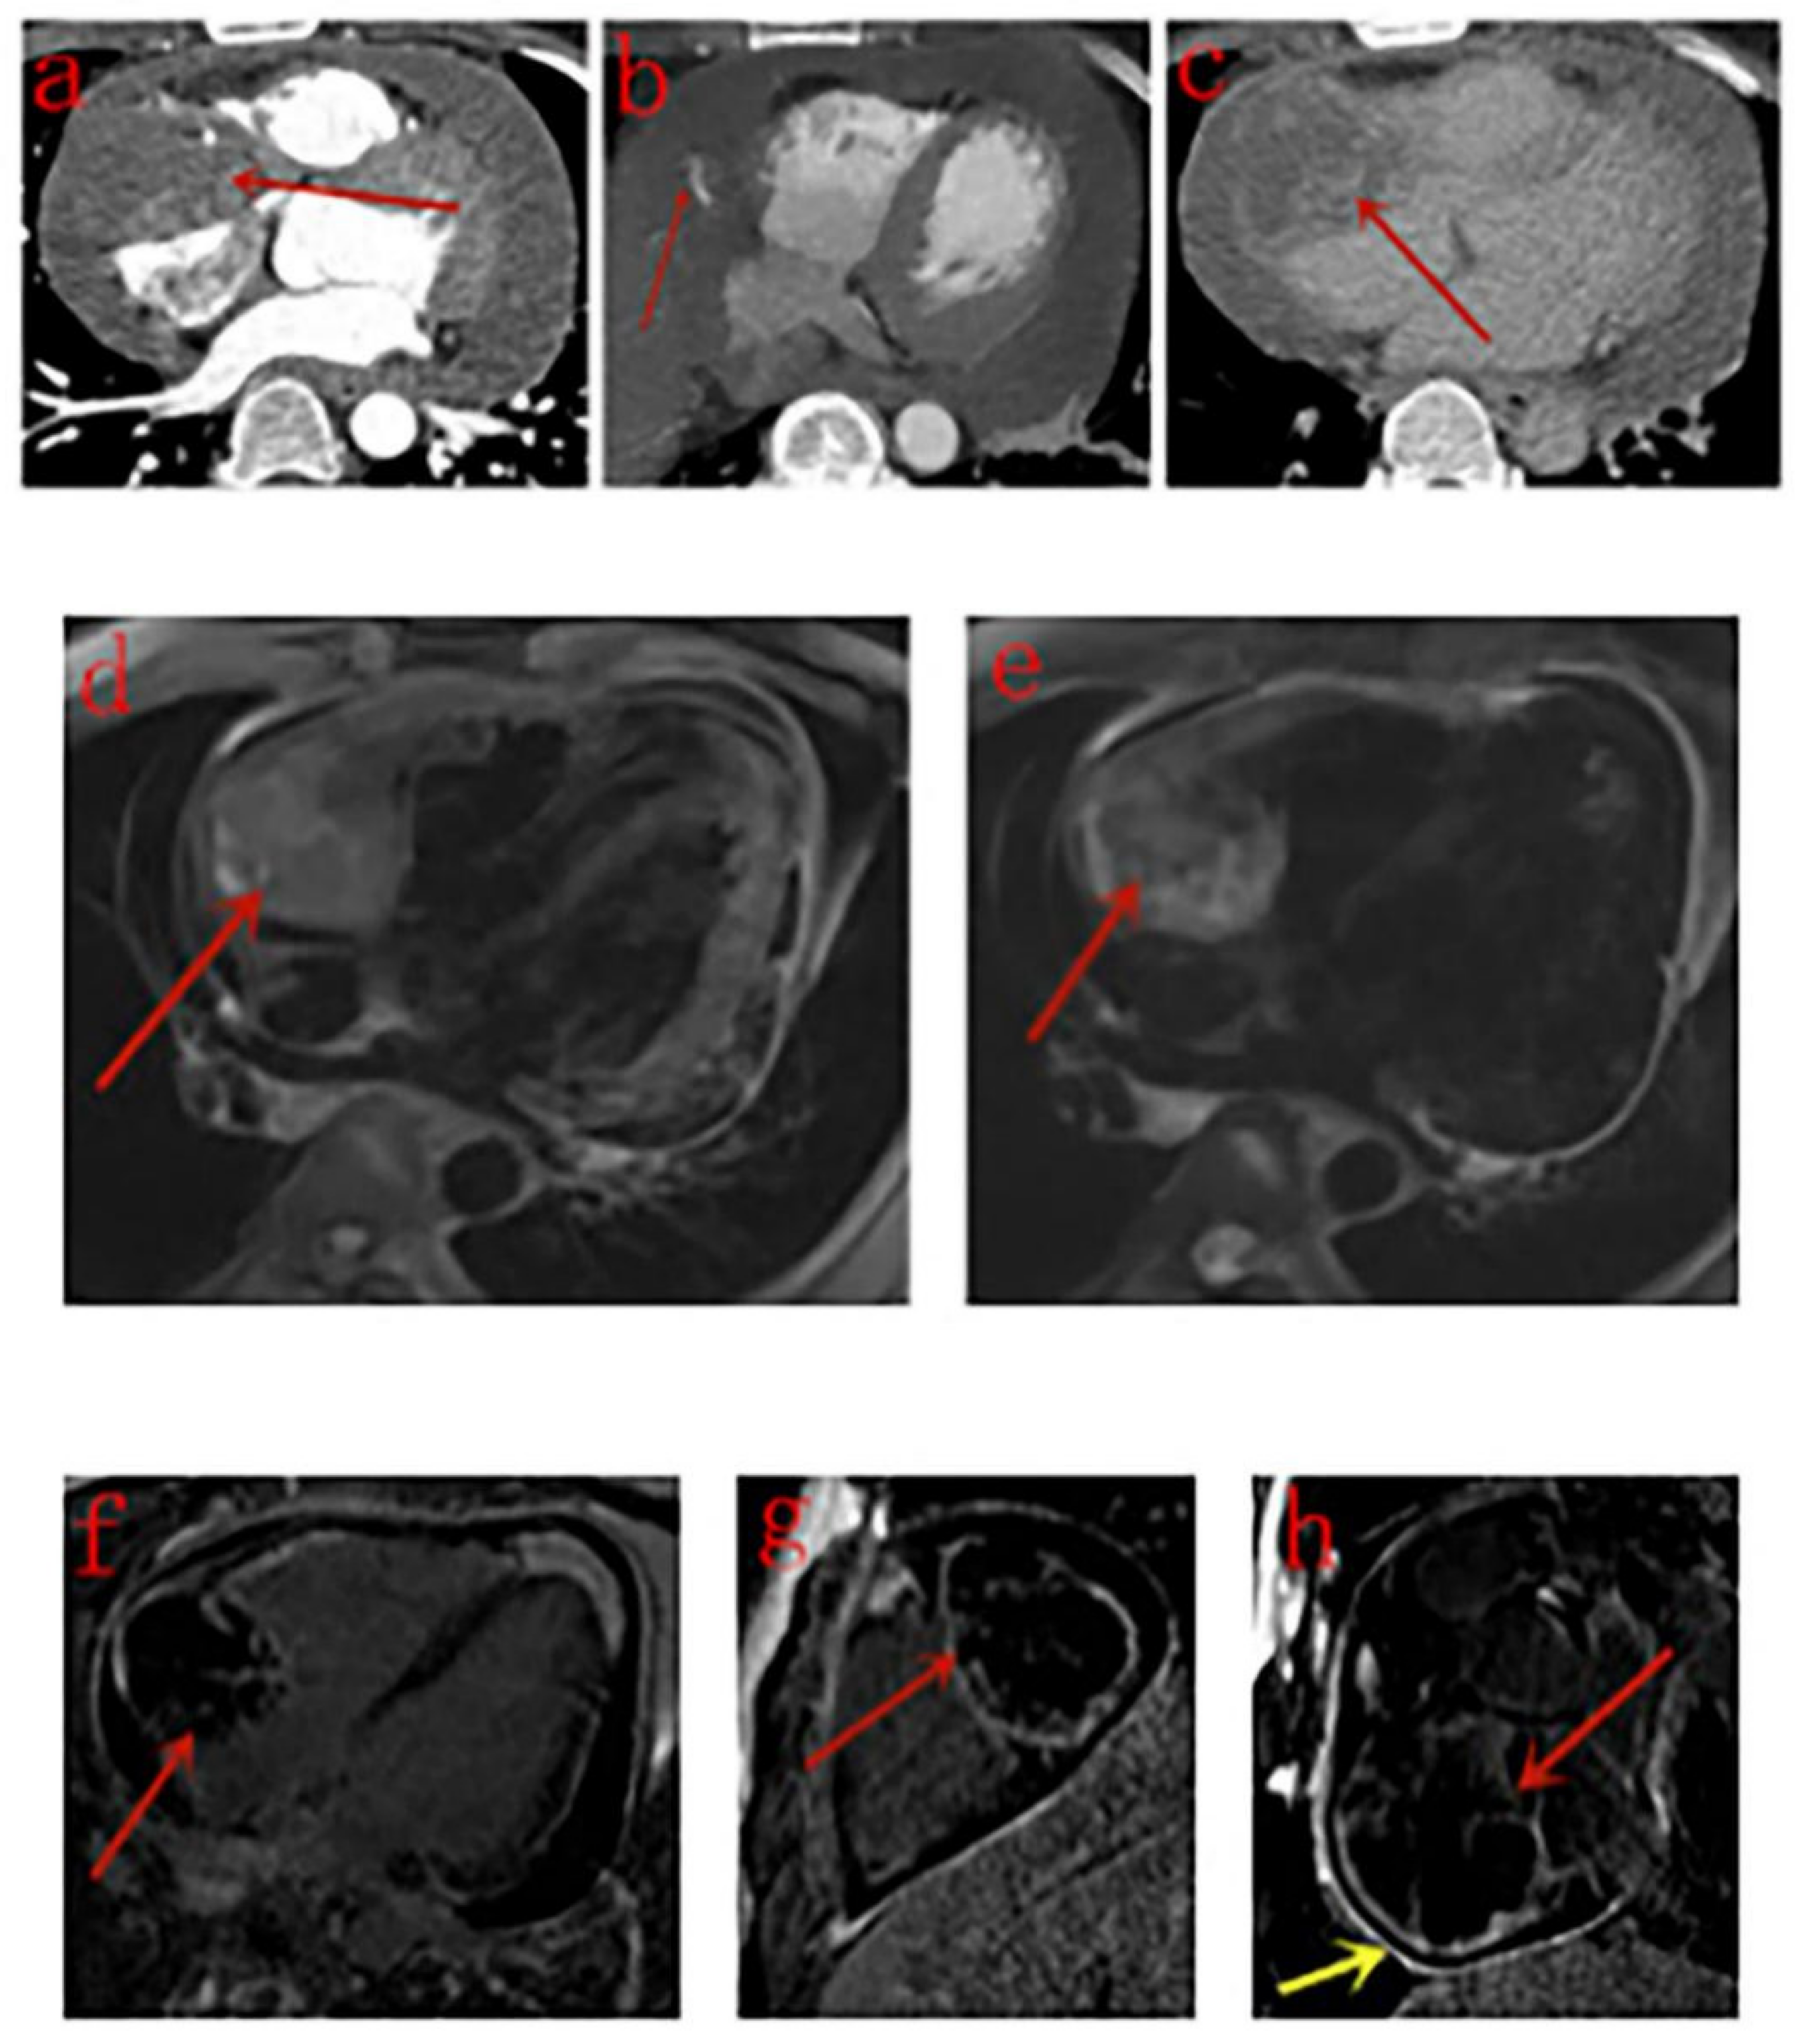

3.3. CT Findings

3.4. MRI Findings

| Our study | 12 | Masses in the right atrium invading pericardium, RCA, RV, SVC and IVC, presented as homogeneous or inhomogeneous on unenhanced CT scans and heterogeneous centripetal enhancement on enhanced CT scans, The enhancement pattern shows no exact correlation with the differentiation degree of the tumor. Pulmonary metastases with halo sign was common. | Masses in the right atrium invading pericardium, RCA, RV, SVC and IVC, presented as cauliflower-like appearance on T1WI and T2WI, signal void was noticed in a lesion with strong enhancement for arterial phase on CT scan. RA and RV motion was severely impaired. Rim enhancement was noticed in 3 patients and patchy enhancement was noticed in one patient. |